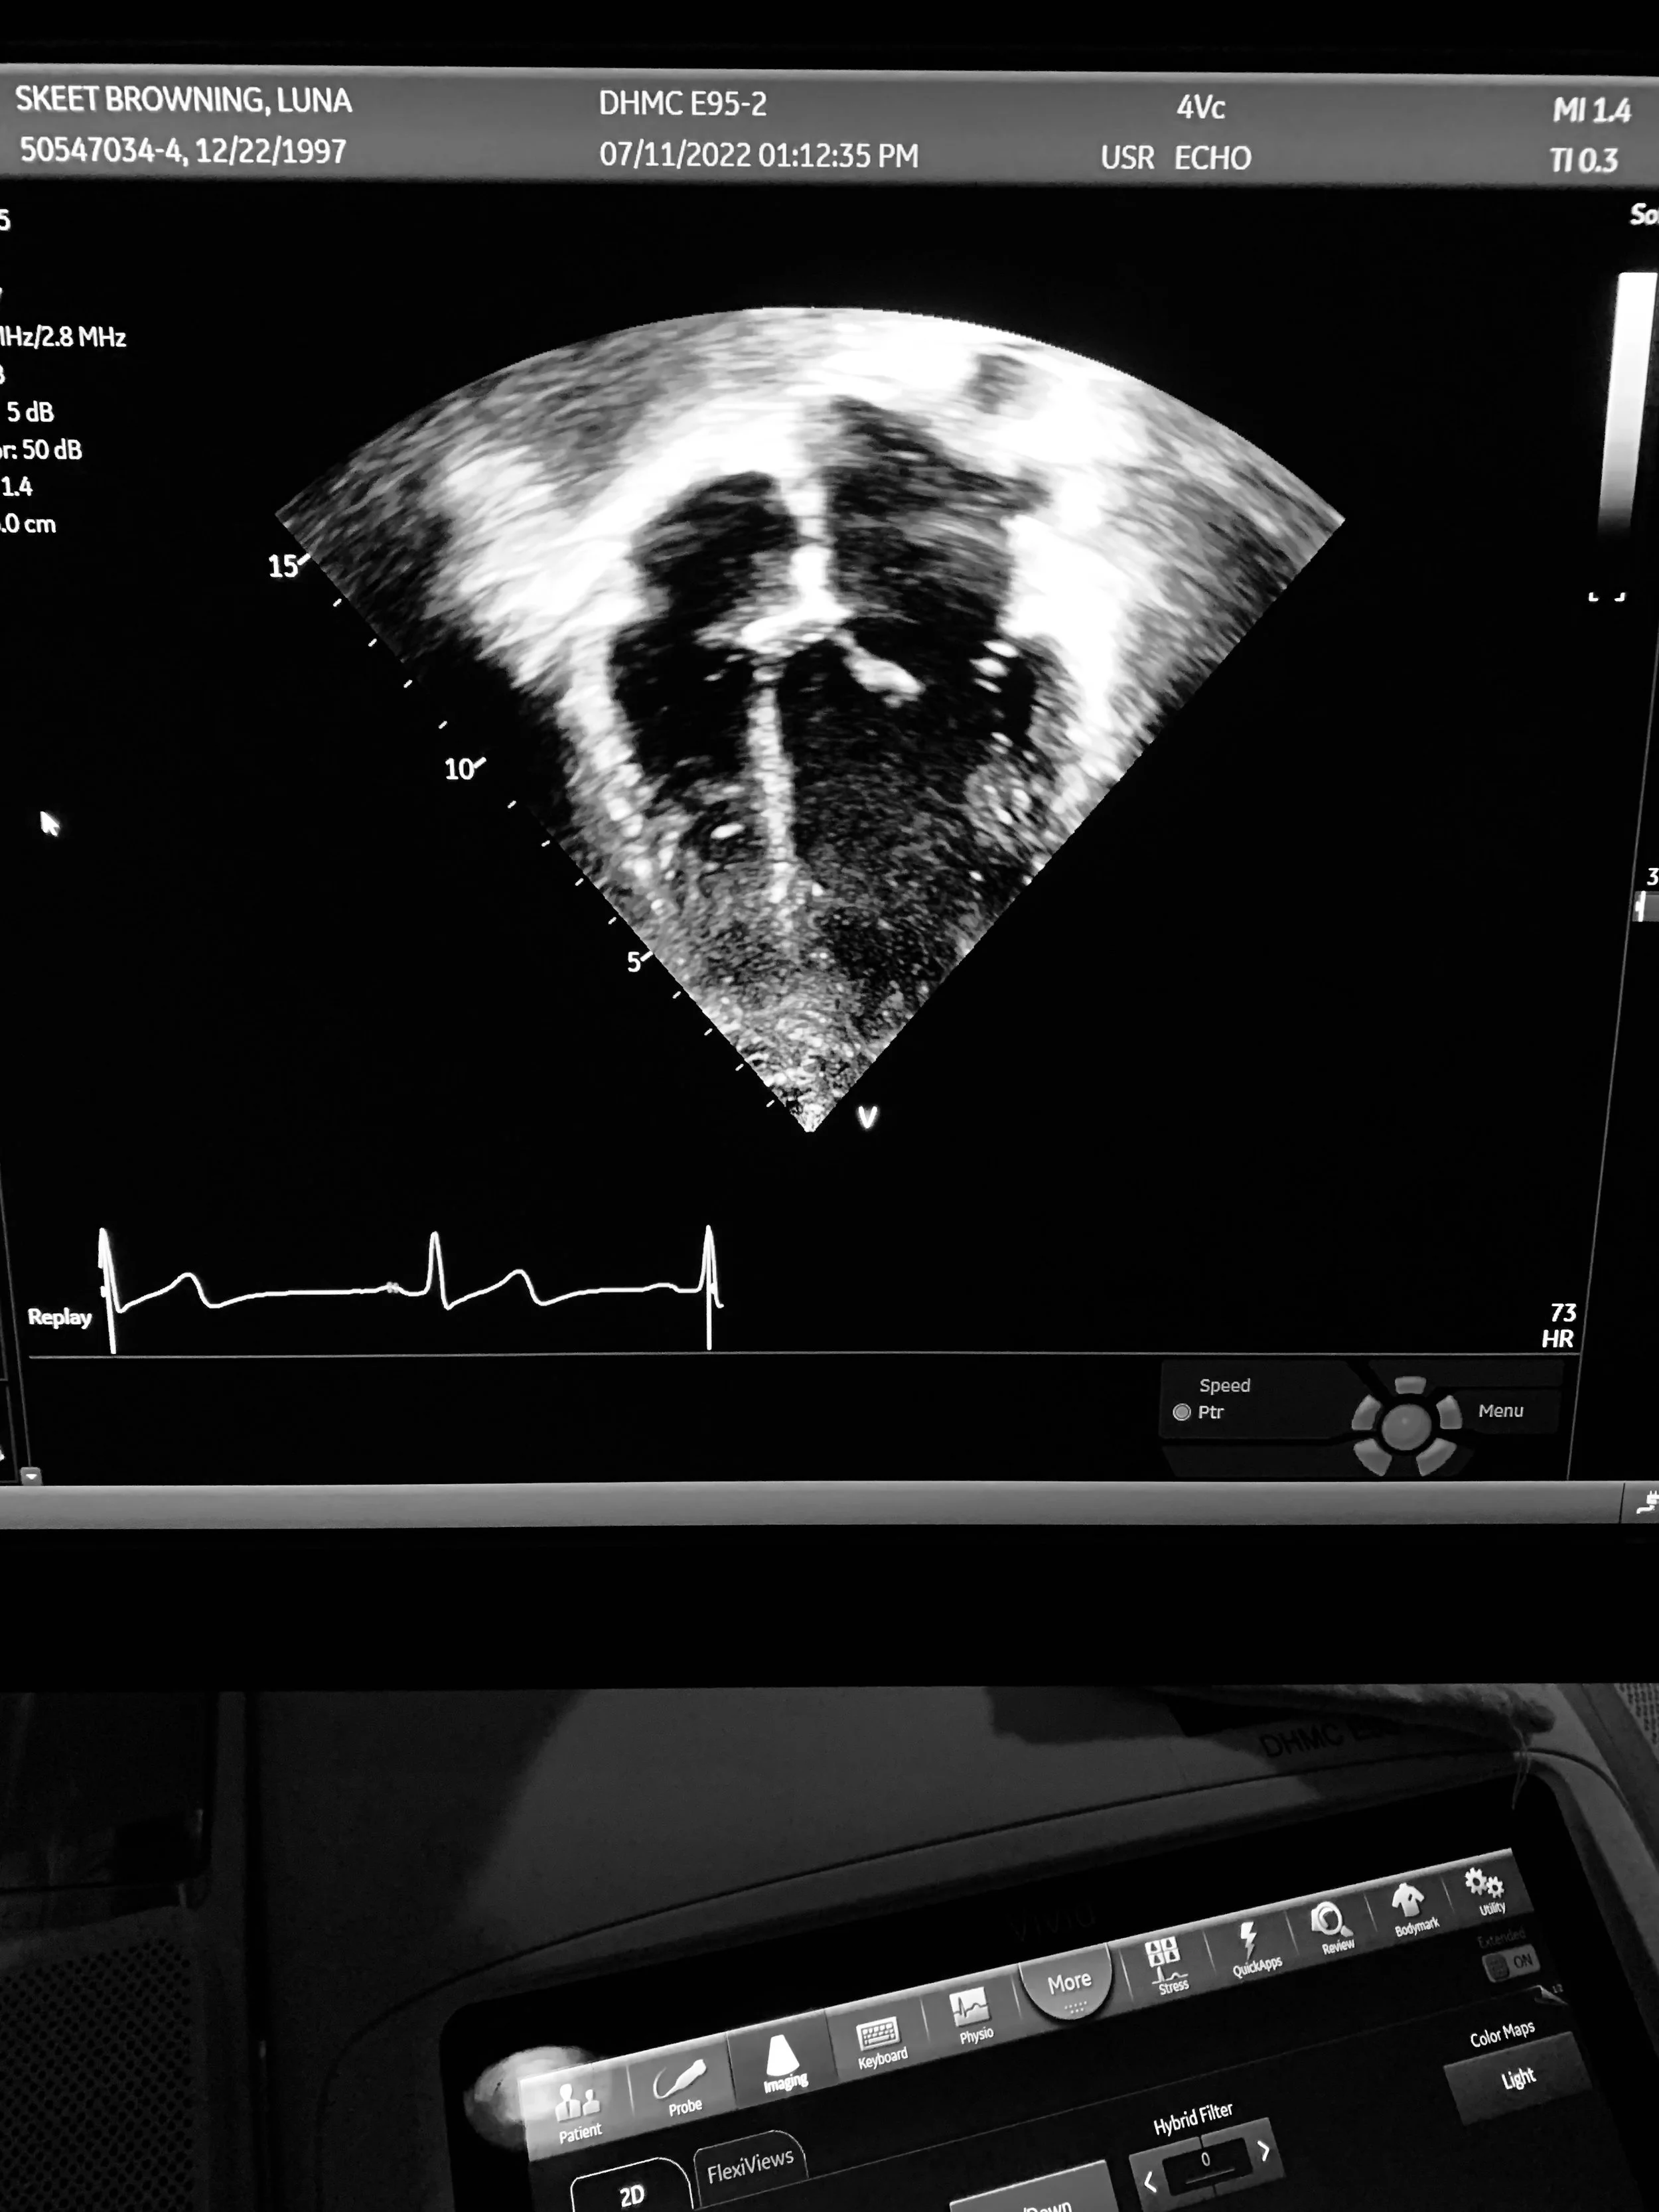

Regarding the (literal) hole in my heart.

There’s a 0.1-0.4% chance of being born with a hole in your heart. Fortunately it hasn’t affected me very much, but every couple of years I have a routine echo to make sure it’s still functioning well. I’ve read about people looking up to a similar image when they’re pregnant and feeling very emotional when they see their baby. And while I wouldn’t know about that particular experience, this is the first time in 24 years that I felt emotional when looking at my heart on the screen.

My body and I have been through a lot together the past few years. At best, I saw it as defective and unruly. At worst, there were some nights, especially when it became very painful to breathe, where I lay awake and worried that maybe I was, in fact, dying. Luckily the way I relate to my body is evolving, but seeing a visual in real time of the surprising force with which my heart is pumping blood nonstop was somewhat of a wakeup call, an undeniable reminder of how hard our bodies are working for us.